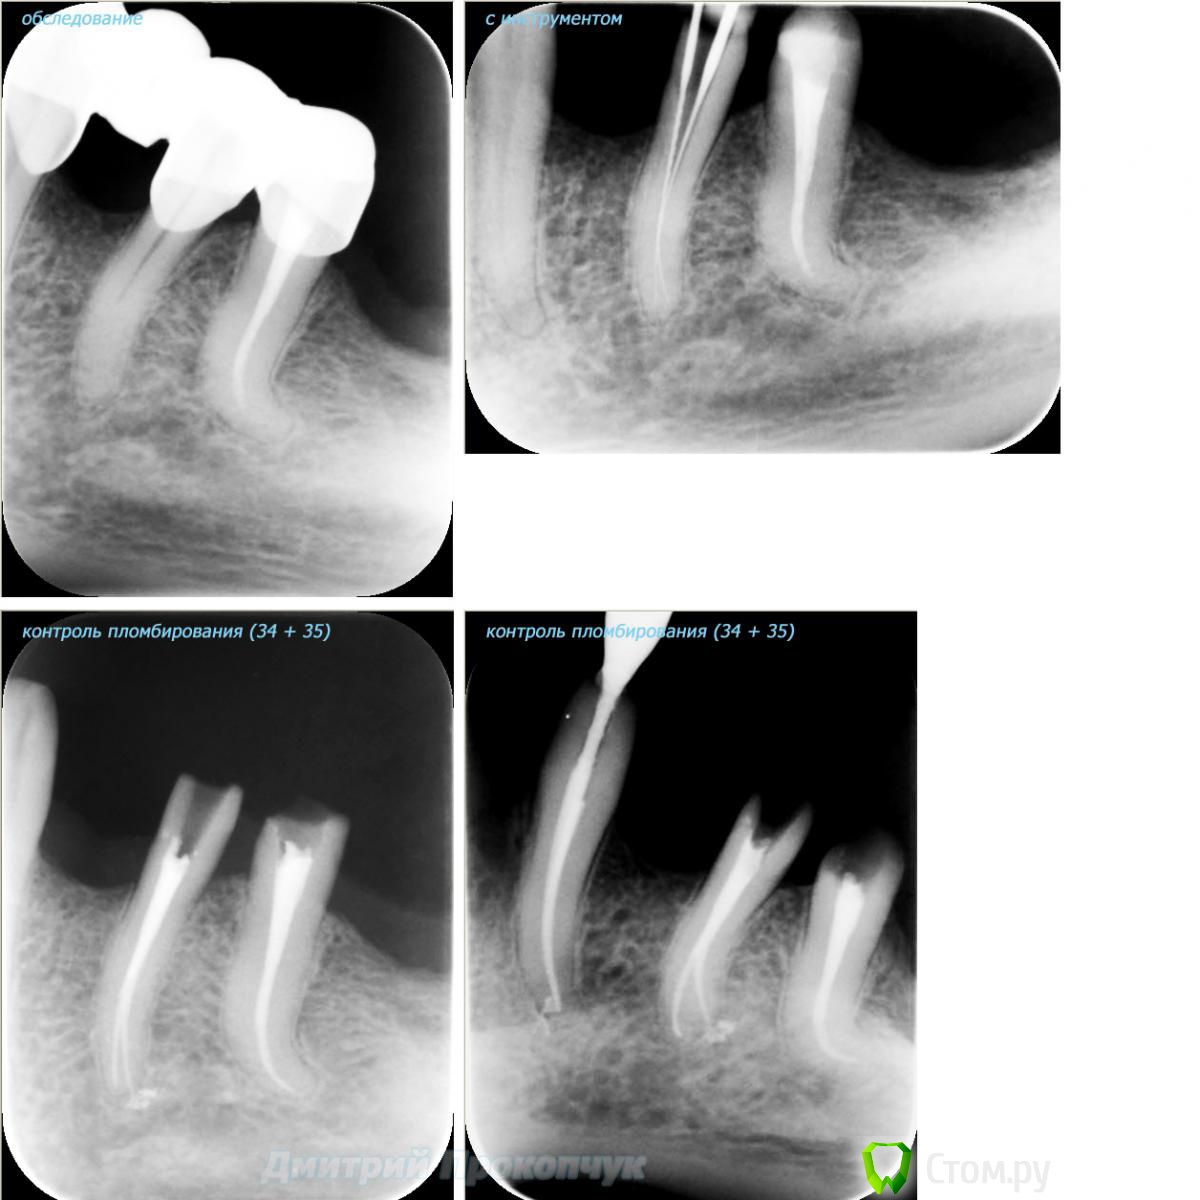

punkrat Опубликовано 16 сентября, 2014 Поделиться Опубликовано 16 сентября, 2014 Коллеги, тема , возможно, не имеет смысла просто приятная мне эндодонтия, сохранил с предыдущего места работы. Да, будь я проклят, я все знаю, НИГДЕ НЕТ КОФЕРА, на новом месте с этим норм. В общем если посчитаете, что я недостоин постить тут свои снимки, то так тому и быть, удалю тему.. 01. плановый ретрит 46ого и результат через 7 месяцев. Осложняющим моментом тут было то, что длина каналов была около 26 мм... 02. первичное эндо 34 (подготовка к ортопедии) + бонус - ретрит 35 03. ретрит 26 (подготовка к ортопедии) 04. ретрит 15, 16 (подготовка к ортопедии). основная сложность была в ретрите 15 - он был запломбирован термафилами, да еще снабжен свш... 05. ретрит 27 (подготовка к ортопедии). Ничего особенного, со временем посмотрим какова будет убыль этого совсем немаленького разрежения 06. ретрит 13. Разумеется пришлось выбивать вкладку, а потом еще попилить 3-4 миллиметра цемента, но, таки попилил куда нужно... 07. ретрит 17 (подготовка к ортопедии). В данном случае я, кажется, потратил больше времени на снятие литого моста, чем на лечение 17)) 08. ретрит 16 (подготовка к ортопедии). Снимка с инструментом нету, поскольку, визиограф сломался и его делал на пленку. 15 разумеется тоже перелечен... 09. плановый ретрит 16 10. первичное эндо 36, рядовой случай что дистальный щечный удалось найти не сразу, он был спрятан под нависающим дентиклем 11. ретрит 12, 11 (подготовка к ортопедии). Казалось бы, рядовой случай, если бы корневые каналы обоих зубов не были бы налухо забиты резорцин-формалиновой смесью... 12. ребенок 9ти лет, острый пульпит 46, попробовал оставить витальным. Пока полет нормальный, но даже если придется делать эндо в последствии, лучше когда оно будет сделано в более старшем возрасте... 13 Ссылка на комментарий